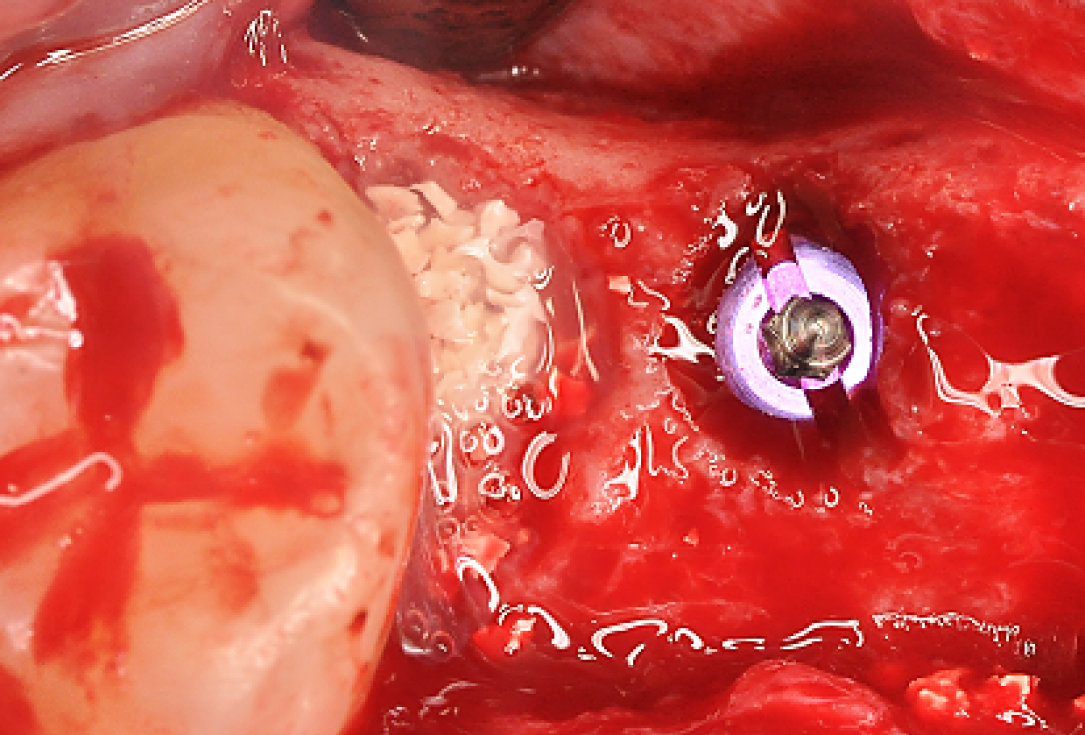

Treatment of a double root fracture in the aesthetic zone with cerabone® – Dr. J. M. Abarca

47 years old patient referred by another dentist after suffering a fall while fishing